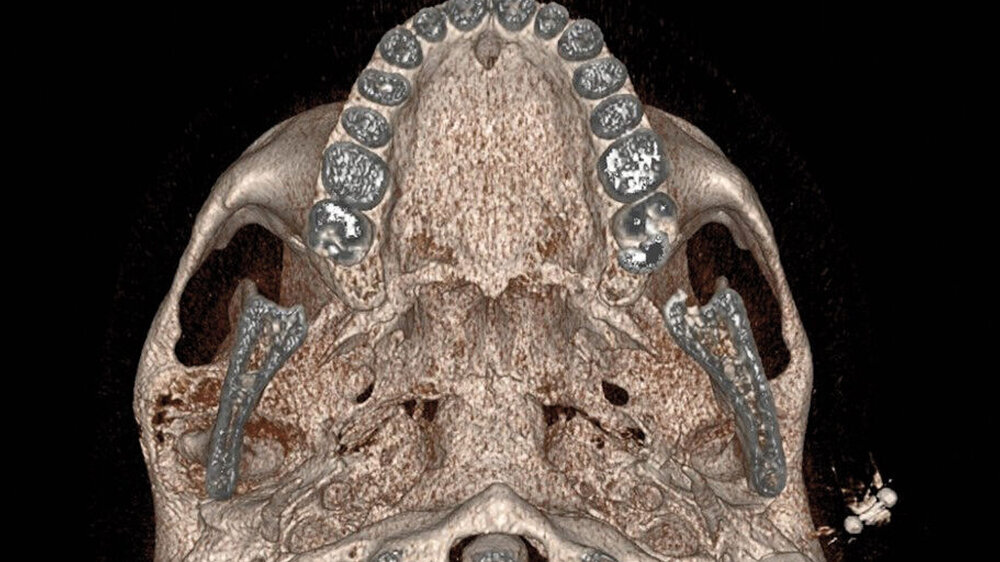

Im MRT und CT zeigte sich eine expansiv wachsende, überwiegend mattglasartige Knochenveränderung mit osteolytischen Anteilen und Unterbrechungen der Knochenstruktur, insbesondere in den unteren Partien nahe dem Kiefergelenk. Die Läsion war mit vermehrter intraossärer Kontrastmittelanreicherung assoziiert, was für eine fibröse Dysplasie spricht. Das Kieferköpfchen war abgeflacht, und es lag eine geringe Flüssigkeitseinlagerung im Kiefergelenk vor. In der Bildgebung fanden sich keine Hinweise auf eine Beeinträchtigung der umliegenden Foramina oder angrenzender Knochenstrukturen wie des Keilbeins (Abbildung 1).

Der Vergleich mit früheren Bildgebungen (MRT 2019 und ältere Schädelröntgenaufnahmen) zeigte ein leicht progredientes Wachstum der Läsion über mehrere Jahre hinweg. Die bildgebenden Befunde und hier insbesondere das umfangreiche Ausmaß der Osteolysen führten zur Empfehlung einer gezielten Biopsie, um eine Malignitätsdiagnose (zum Beispiel Osteosarkom oder Chondrosarkom; aber auch maligne Entartung einer fibrösen Dysplasie) auszuschließen und die Läsion histologisch zu charakterisieren.